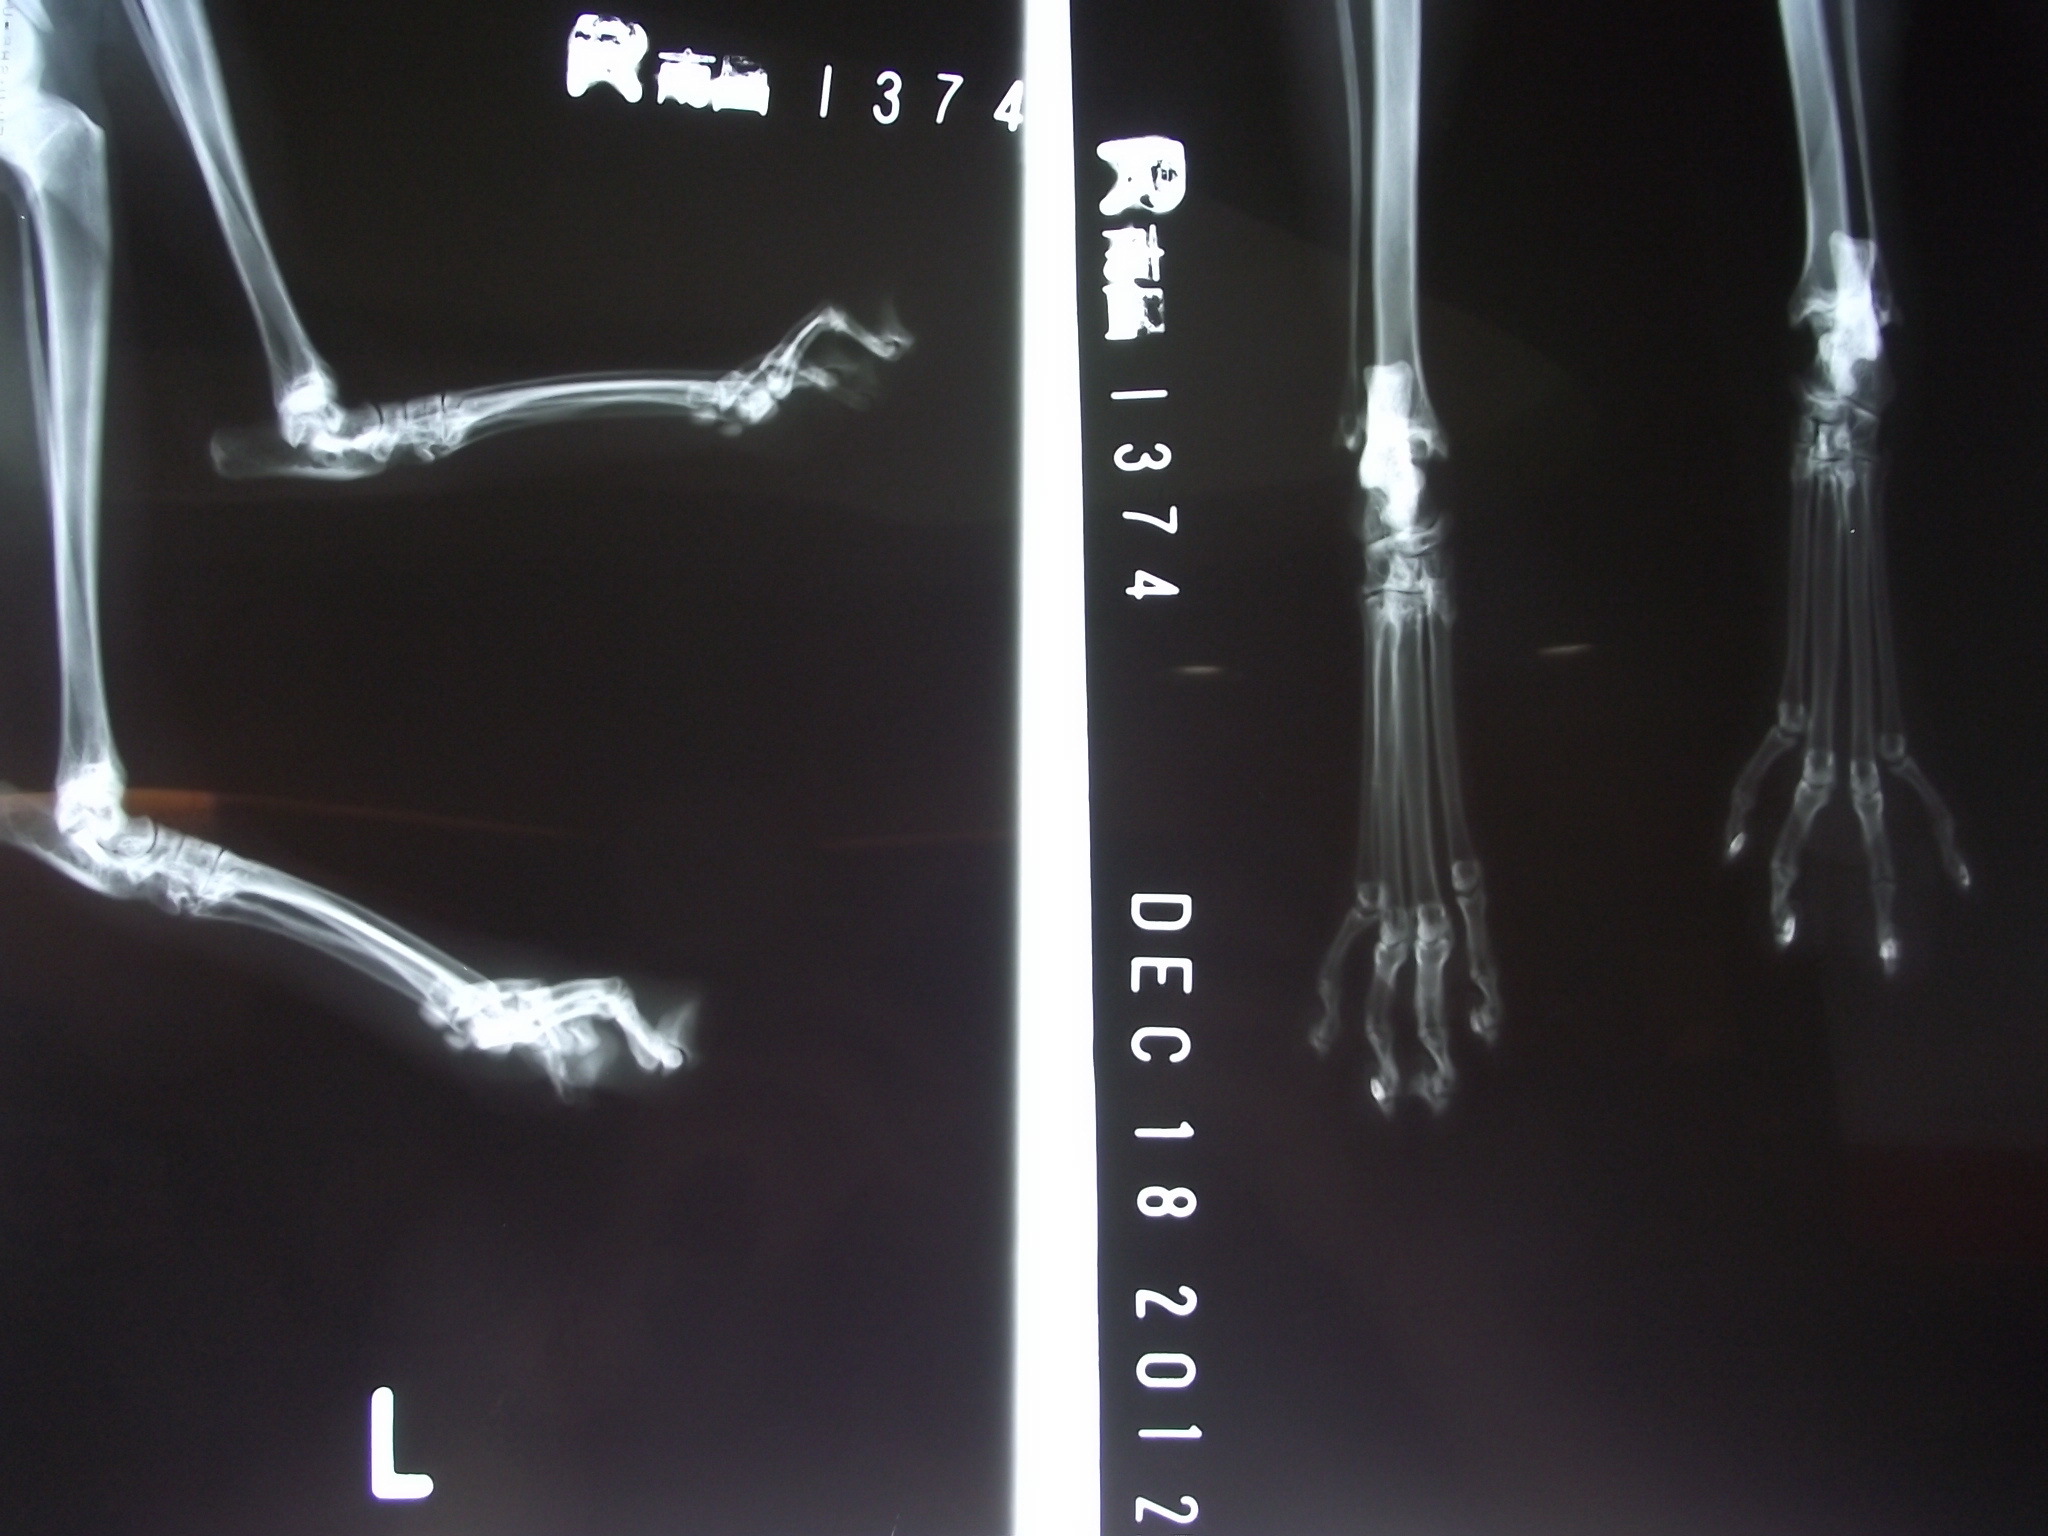

主題: 不明外傷之瘸腳公貓 申請者姓名: 楊珊米 花色: 申請日期: 2012-12-21 16:40:26 申請者部落格: 申請者臉書網址: 所在縣市/合作醫院: 台北市/康廷動物醫院 治療費用: 4400元 需求人數: 10人 已結案 (2013-02-23 14:29:59) 報名人員: 李恩(已付款)、李恩(已付款)、kaidoubibi(已付款)、Summer(已付款)、Fiona(已付款)、eklava(已付款)、Ellen Wang(已付款)、Ou Han(已付款)、皇(已付款)、皇(已付款)、 候補人員: eklava、 動物病情說明: 此為愛貓人李小姐每日固定餵養之街貓,前兩週注意到有瘸腳狀況,僅用三隻腳跳走,原本活潑親人的個性變得怕人畏縮,經觀察一周無好轉現象,故捕捉送至康廷動物醫院處理。

經廖醫師診治為不明外傷,化膿嚴重,深可見骨,照X光後幸未傷至骨頭,經外用藥與口服藥雙管齊下,傷勢好轉後,並做節紮手術。